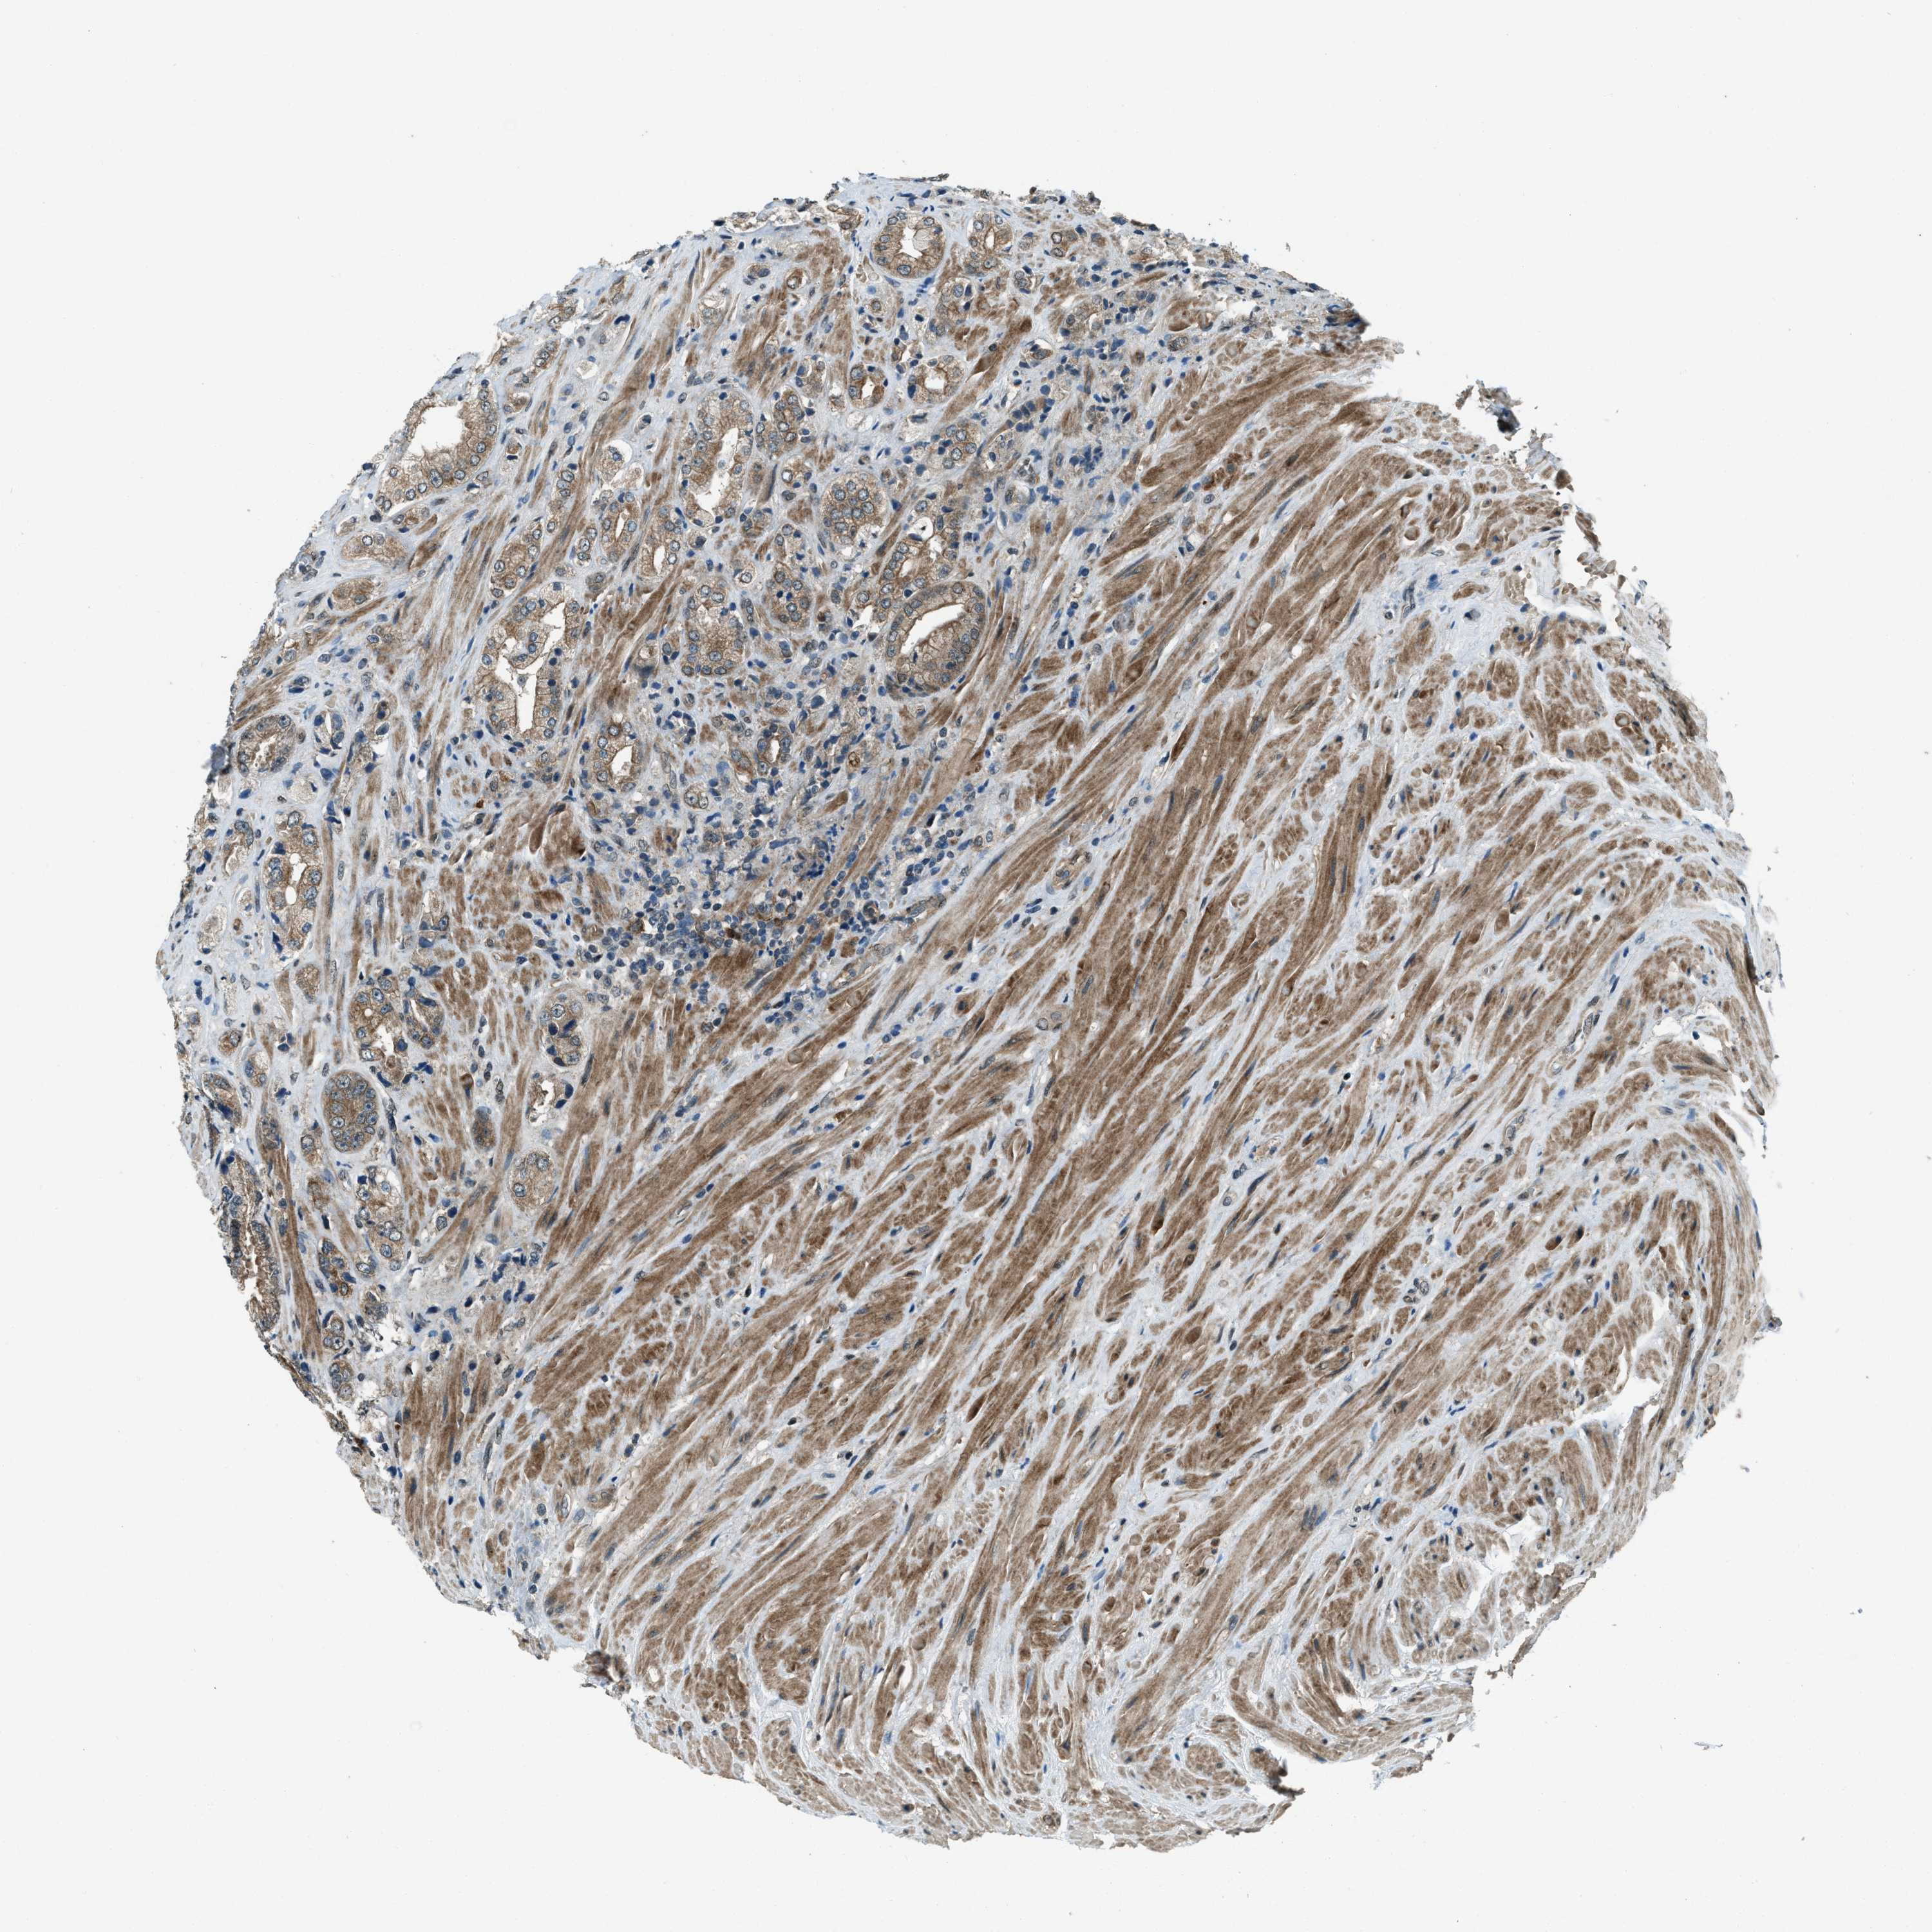

PROSTATE CANCER - Protein expressioni

A mouse-over function shows sample information and annotation data. Click on an image to view it in a full screen mode. Samples can be filtered based on level of antibody staining by selecting one or several of the following categories: high, medium, low and not detected. The assay and annotation is described here.

Note that samples used for immunohistochemistry by the Human Protein Atlas do not correspond to samples in the TCGA dataset.

Antibody stainingi

Antibody staining in the annotated cell types in the current human tissue is reported as not detected, low, medium, or high, based on conventional immunohistochemistry profiling in selected tissues. This score is based on the combination of the staining intensity and fraction of stained cells.

Each image is clickable and will lead to virtual microscopy that enables deeper exploration of all samples and also displays staining intensity scores, fraction scores and subcellular localization as well as patient and tissue information for each sample.

Antibody HPA020095

Antibody HPA020138

Antibody CAB010878

Antibody CAB080402

Staining

High

Medium

Low

Not detected

Intensity

Strong

Moderate

Weak

Negative

Quantity

>75%

75%-25%

<25%

None

Location

Nuclear

Cytoplasmic/membranous

Cytoplasmic/membranous,nuclear

Adenocarcinoma, High grade

Adenocarcinoma, Low grade

Adenocarcinoma, NOS

Adenocarcinoma, Medium grade